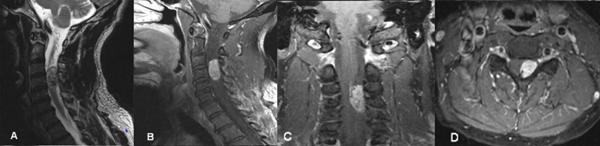

Fig 1. Caso 1. RMN: T2 sagital (A) y T1 con contraste sagital (B) coronal (C) y axial (D) que evidencia lesión nodular intradural extramedular C3-C4 a izquierda, con realce homogéneo post contraste que desplaza y comprime la médula en sentido lateral.